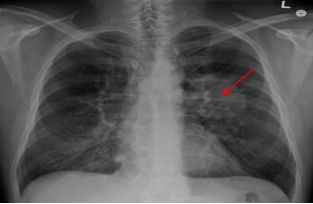

根據(jù)美國癌癥協(xié)會(huì)的報(bào)告,肺癌導(dǎo)致男性和女性癌癥死亡人數(shù)最多,并且它在我國的發(fā)病率、致死率一直排在第一位。肺癌進(jìn)展快,通常采用放化療的方式來延緩癌癥的進(jìn)展,到這種種方式,糾其根本,都是引發(fā)癌細(xì)胞不可逆性損傷來治療腫瘤。

肺癌胸片